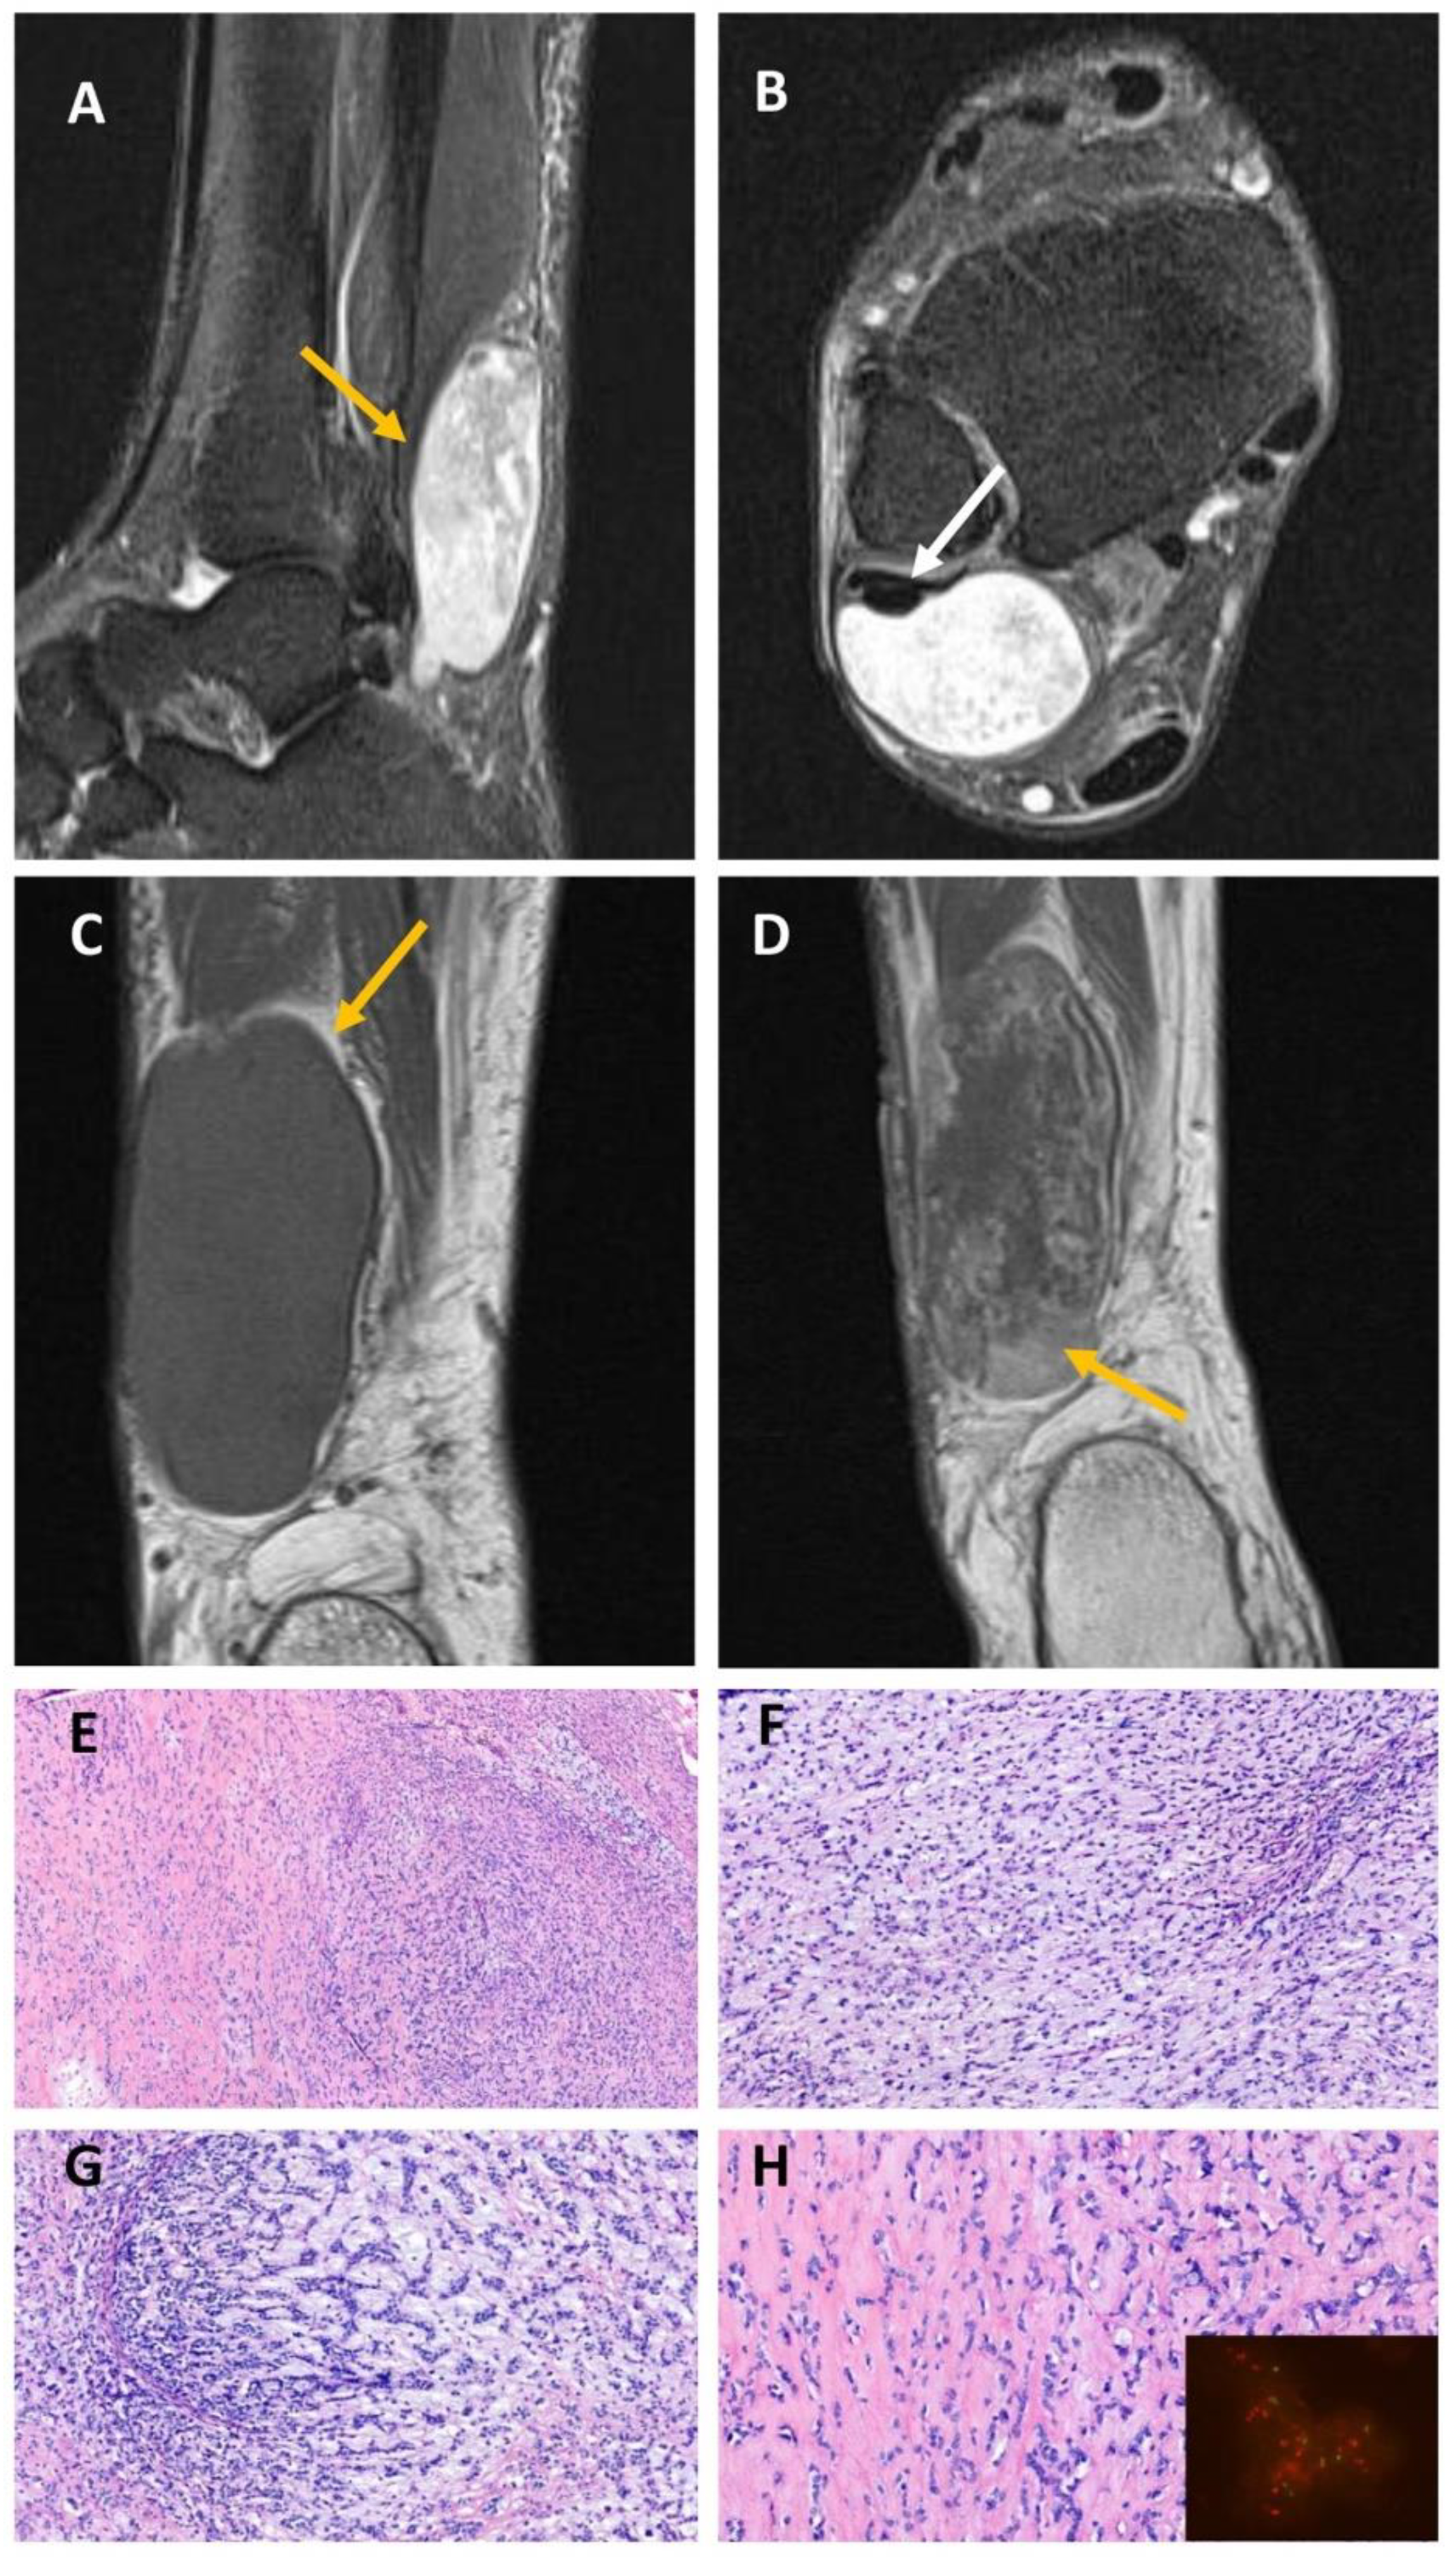

2.3. EWSR1::NFATC2-Rearranged Soft Tissue Sarcoma (Case #4)